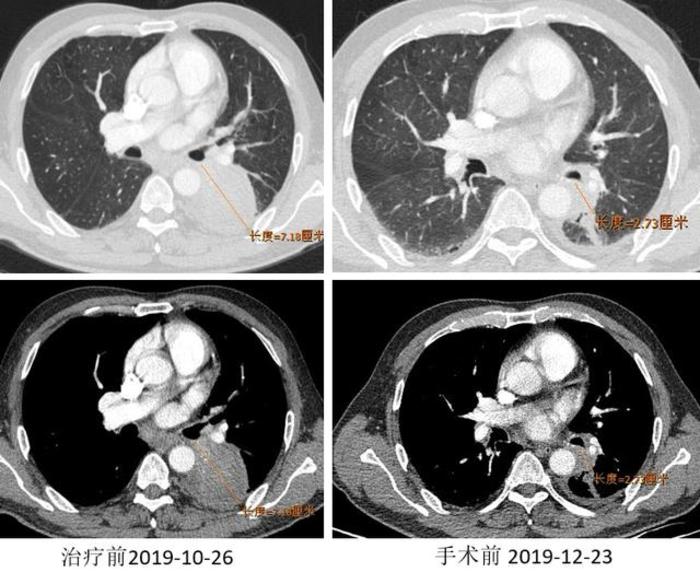

基本情况:患者,男,64岁。2019.10.11 因“痰中带血半月”入院。穿刺病理:(左下叶)鳞癌。免疫组化结果:PD-L1(22C3)(-) 。基因检测:无基因突变。支气管镜:左下叶背段见新生物,部分堵塞左下叶管腔。超声下见7组淋巴结肿大及左肺病灶影。临床分期:cT4N1M0-ⅢA

诊疗经过:两周期免疫治疗联合化疗方案。2019.01.03 行“VATS辅助左肺下叶切除术”。

术后冰冻病理:(左下叶)见少量异型细胞,病灶内见纤维组织伴淋巴组织增生、组织细胞聚集、胆固醇结晶沉积及反应性多核巨细胞,结合病史符合新辅助治疗后反应(MPR,即治疗后病灶内残留癌细胞<10%)。(第11组淋巴结)肺组织内见纤维组织增生伴炎细胞浸润及组织细胞反应。

又是一例驱动基因突变阴性的患者,连PD-1/PD-L1突变都没有,相比较于之前我们分享的病例,却获得了更好的疗效,达到了MPR。